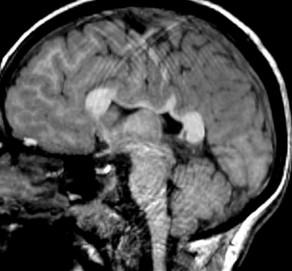

Where is the vermis? Big or small?

Do you have a normal fastigial point?

What is the abnormal horizontally oriented structure? What is the diagnosis?

Where is the vermis? Big or small? Too small…

Do you have a normal fastigial point? Yes, pointed… What is the abnormal horizontally oriented structure? the superior cerebellar peducle…

What is the diagnosis?

What is the yellow arrow pointing to?

“molar tooth” midbrain

Large horizontally oriented superior cerebellar peduncles

Small, dysplastic vermis

“bat wing” 4th ventricle configuration

Associated with:

Absence of decussation of WM pathways in brain stem on DTI

Supratentorial:

Absent septum pellucidum

Fused fornices

Ventriculomegaly

Polymicrogyria